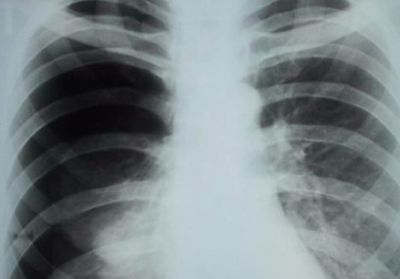

Пневмония

Характер и локализация боли

Правостороннее воспаление легкого характеризуется тупой болью в правом боку, локализованной преимущественно в подреберье.

Диагностика и лечение

При возникновении описанных выше симптомов необходимо обратиться к пульмонологу, который проведет осмотр и сбор анамнеза и назначит дополнительные диагностические процедуры, включающие:

- рентгенографию;

- КТ;